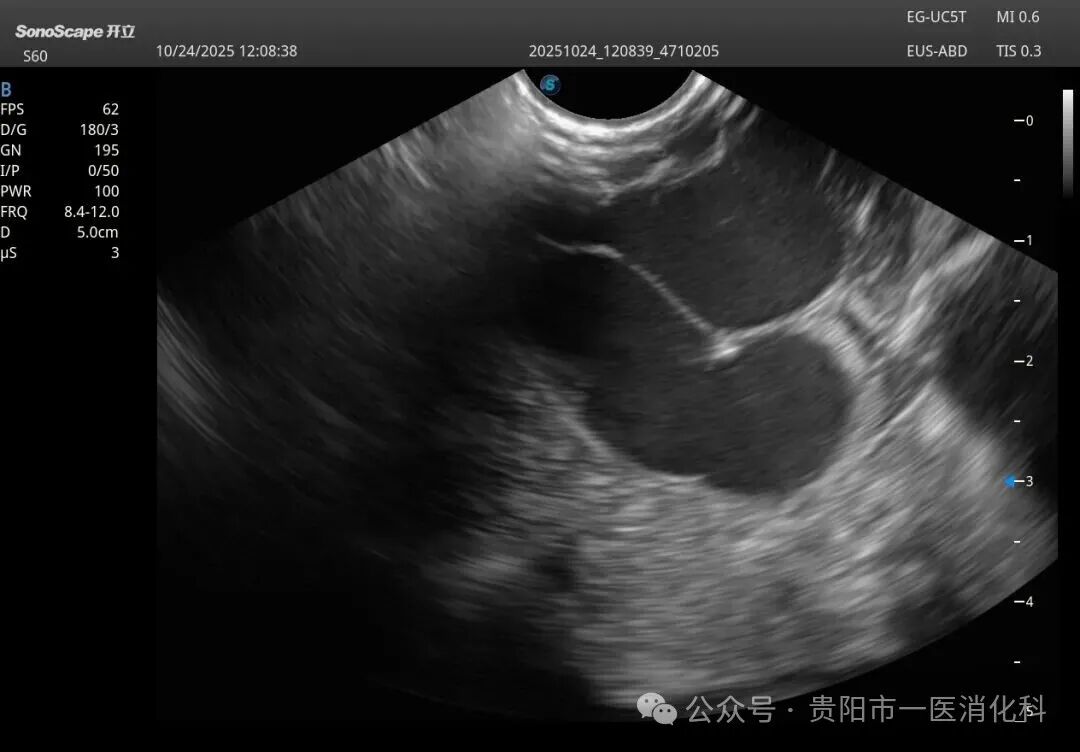

在王俊雄教授的全程指导下,手术如期进行。术中,专家团队首先将超声内镜送达胃底,屏幕上立即清晰显示出曲张静脉的横断面、深度、血流以及其来源血管。在超声的“火眼金睛”引导下,穿刺针犹如被安装了“GPS导航”,精准刺入目标血管。随后,医生们先将数个微弹簧圈送入血管内,构建一个坚实的“巢”,再注入医用组织胶水。弹簧圈与组织胶迅速结合,形成稳固的复合栓塞物,彻底封堵了致命的曲张静脉。整个手术过程流畅,术后患者生命体征平稳,安返病房。